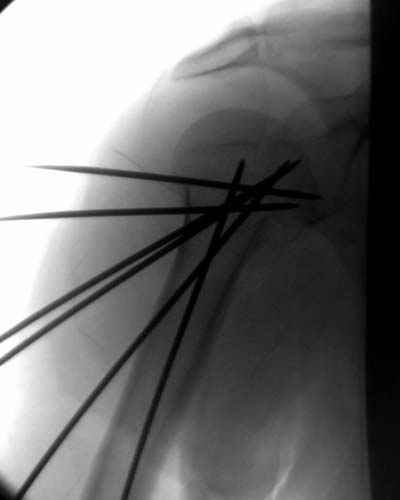

Здесь случай перелома-вывиха плеча, больному 56 лет, после "дважды" закрытой неудачной репозиции, опять же ургентно взяли в операционную, после полного общего обезболивания попытались сделать репозицию, и фиксацию провели спицами.

Больной находился в повязке, примерно напоминяющей косыночную, рекомендованы движения в локтевом суставе и маятниковые движения в плече, спицы удалены в три недели (были случаи миграции)

Больной амбулаторный, предупрежден на случай осложнения АВН головки.